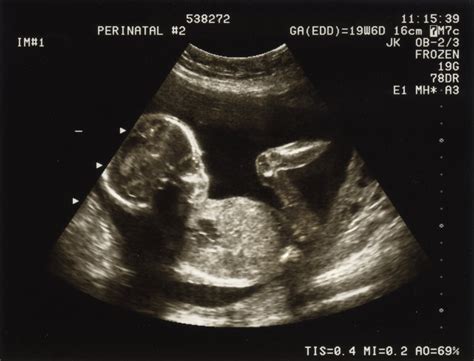

Descoperirea unei posibile afecțiuni de tip picior strâmb în timpul ecografiilor de sarcină, în special în jurul săptămânii a 20-a, declanșează, de regulă, efectuarea unei a doua ecografii pentru confirmare. În acest stadiu, sarcina nu este afectată, iar părinții sunt îndrumați către un medic ortoped pentru a discuta detaliile situației.